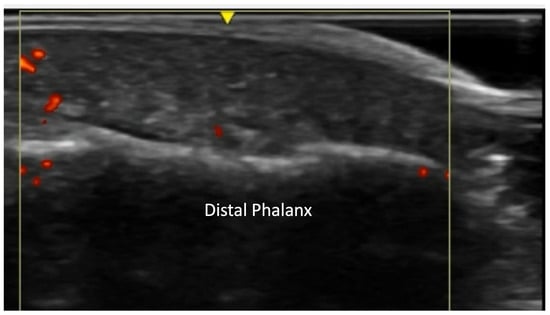

2.4. Vascular Pathology

2.5. Skin Thickening

- Frerix, M.; Stegbauer, J.; Dragun, D.; Kreuter, A.; Weiner, S.M. Ulnar artery occlusion is predictive of digital ulcers in SSc: A duplex sonography study. Rheumatol. Oxf. Engl. 2012, 51, 735–742. [Google Scholar] [CrossRef] [PubMed]

- Lescoat, A.; Coiffier, G.; Rouil, A.; Droitcourt, C.; Cazalets, C.; de Carlan, M.; Perdriger, A.; Jégo, P. Vascular Evaluation of the Hand by Power Doppler Ultrasonography and New Predictive Markers of Ischemic Digital Ulcers in Systemic Sclerosis: Results of a Prospective Pilot Study. Arthritis Care Res. 2017, 69, 543–551. [Google Scholar] [CrossRef] [PubMed]

- Lescoat, A.; Yelnik, C.M.; Coiffier, G.; Wargny, M.; Lamotte, C.; Cazalets, C.; Belhomme, N.; Ballerie, A.; Hatron, P.; Launay, D.; et al. Ulnar Artery Occlusion and Severity Markers of Vasculopathy in Systemic Sclerosis: A Multicenter Cross-Sectional Study. Arthritis Rheumatol. 2019, 71, 983–990. [Google Scholar] [CrossRef]